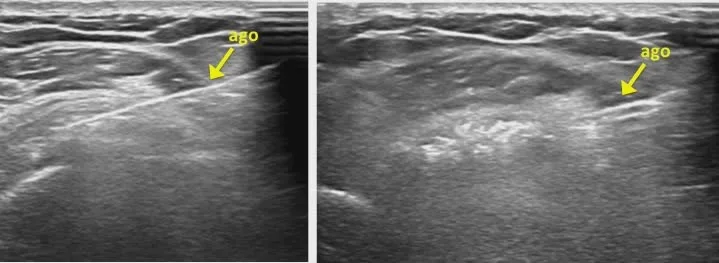

Posizionamento preciso degli aghi sotto guida ecografica per il trattamento della tendinopatia calcifica

i 2 aghi posizionati sotto guida ecografica

Ecografia che mostra il posizionamento degli aghi per il trattamento della tendinopatia calcifica.

le immagini ecografiche dimostrano la corretta posizione dell’ago